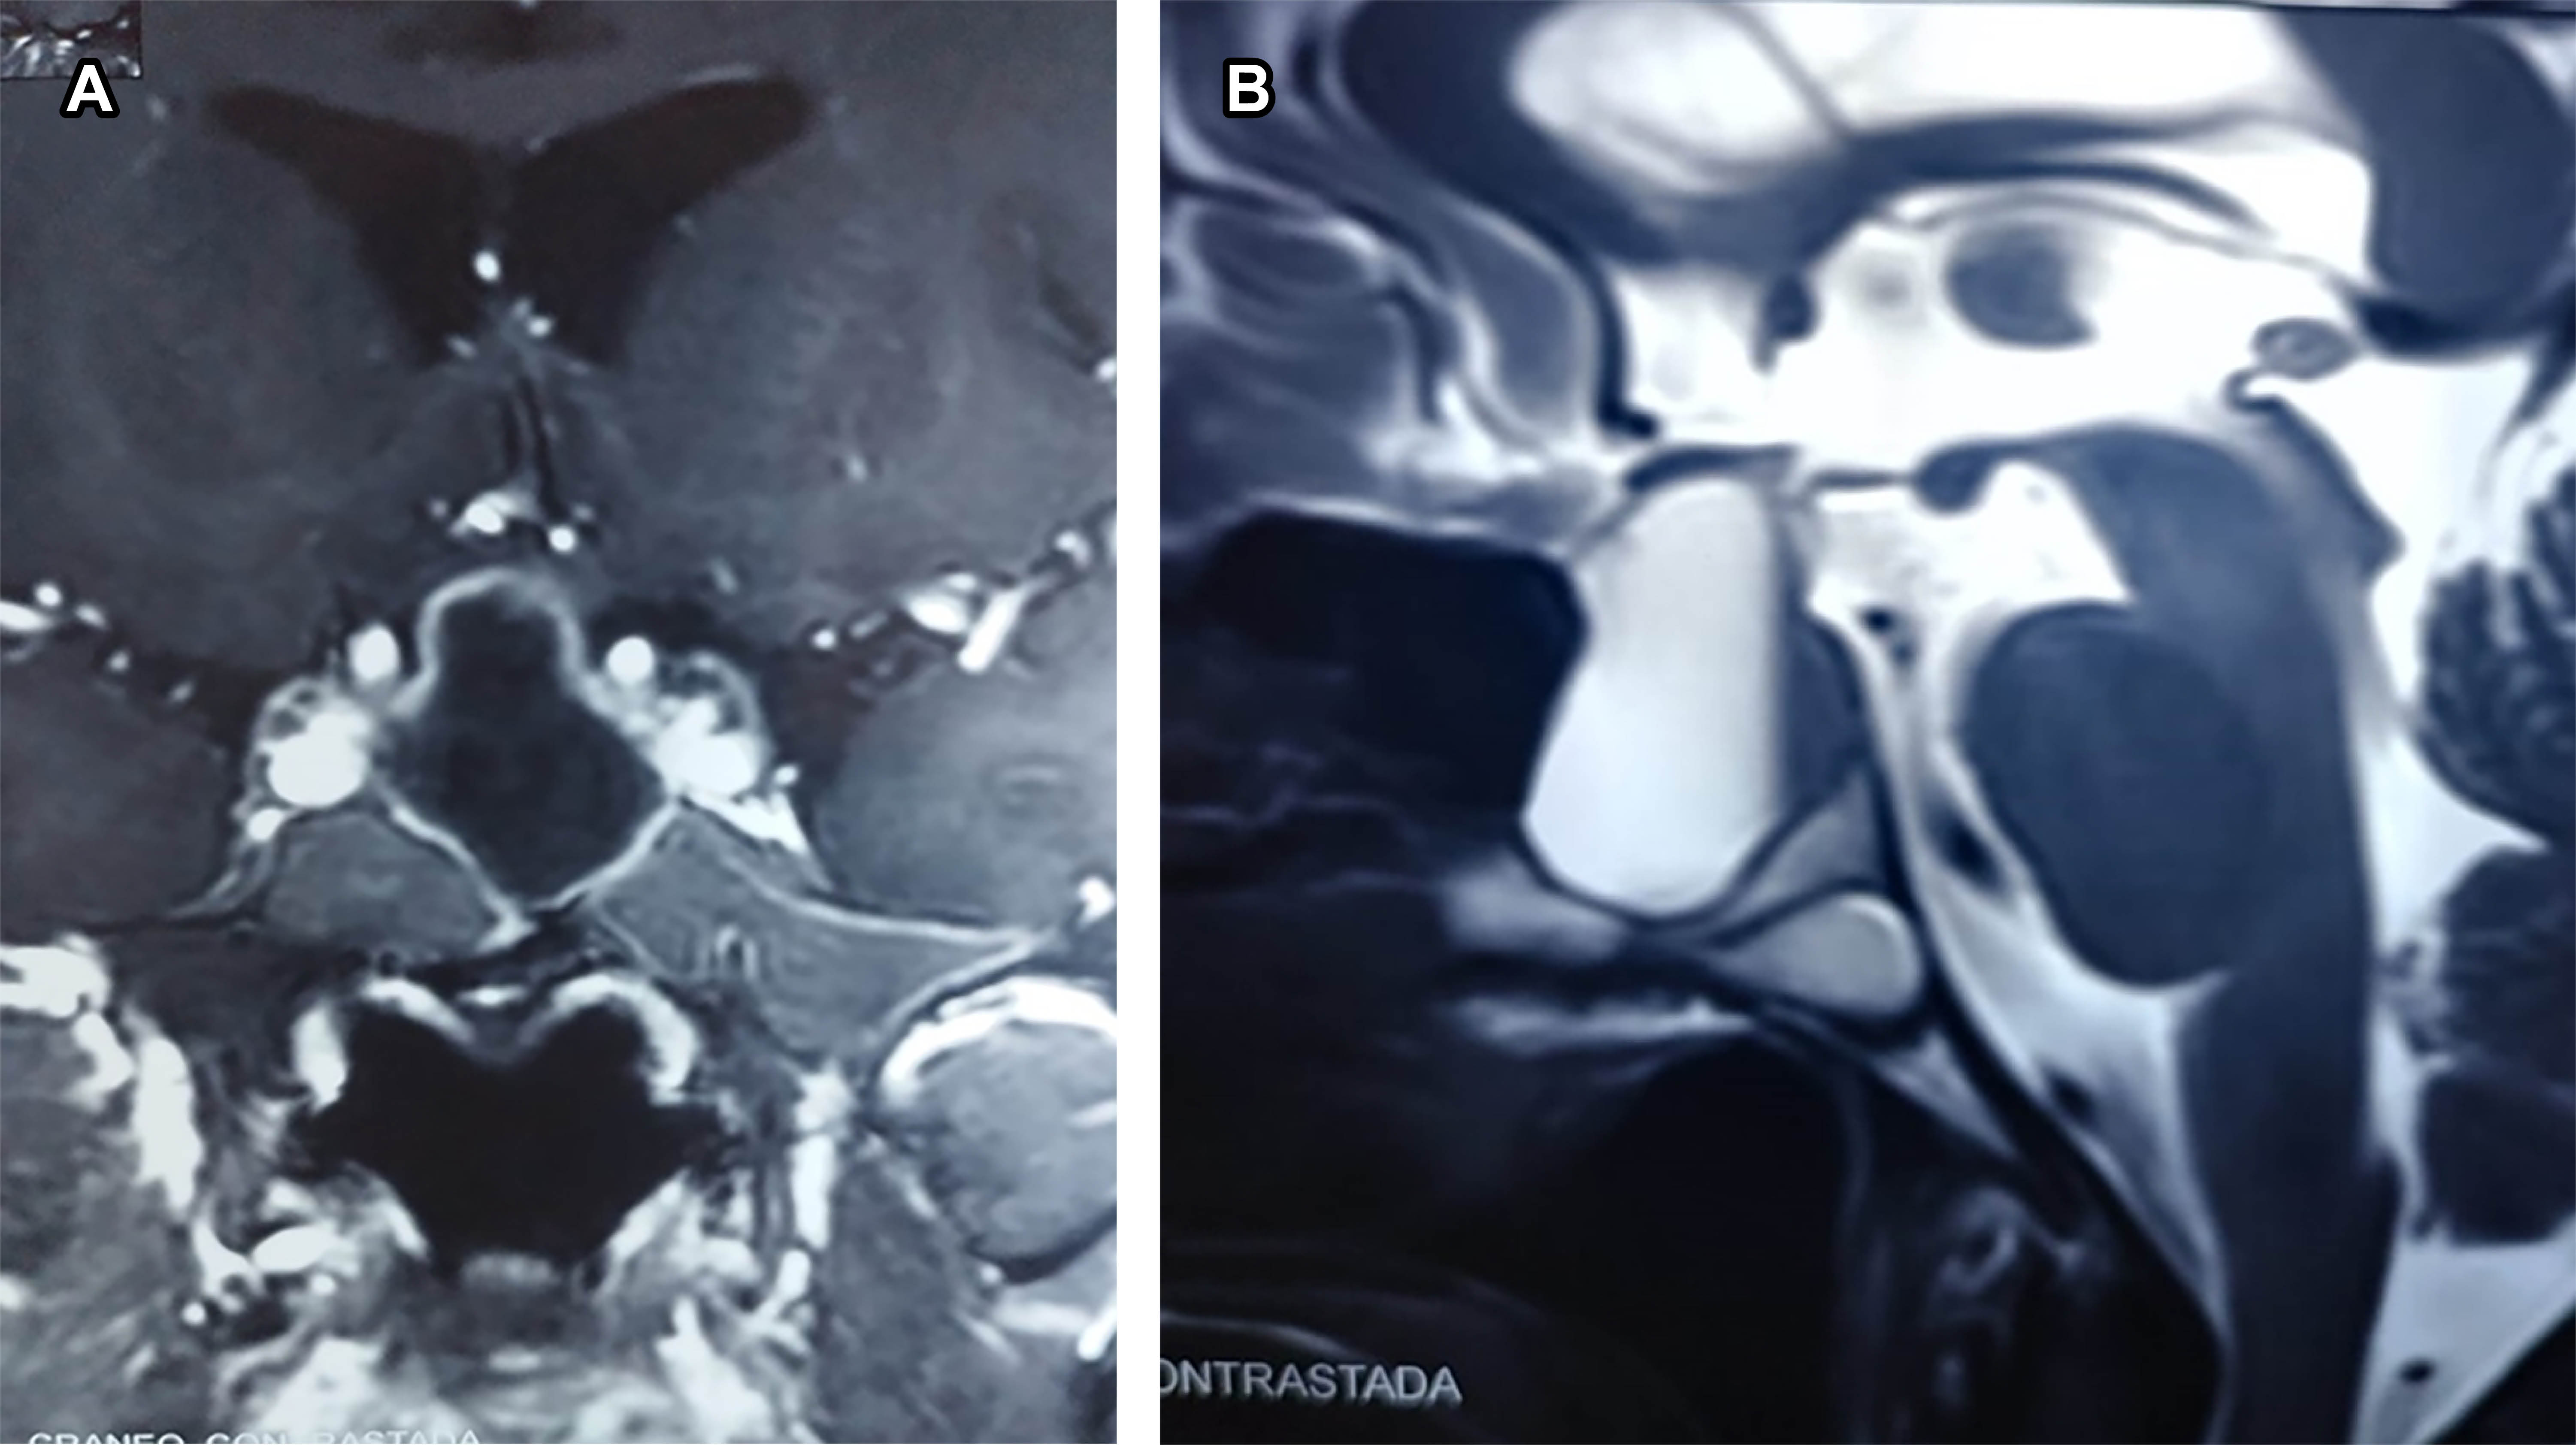

Recurrence of Rathke's pouch cyst: a clinical case

Rathke's cyst is rare, representing less than 1% of primary brain masses, and usually asymptomatic. As it grows, it causes generalized headaches, diplopia, and blurred vision due to compression of neighboring structures. It originates from Rathke's pouch, which is an ectodermal invagination in the stomodeum that, between the third and fourth week, grows dorsally towards the infundibulum, giving rise to the adenohypophysis. MRI shows a hyperintense mass on T1, hyperintense, or isointense on T2; the cyst does not enhance with contrast medium. Surgery is the treatment of choice. Recurrence increases exponentially after 72 months.

Figure 1

Figure 2

Figure 3